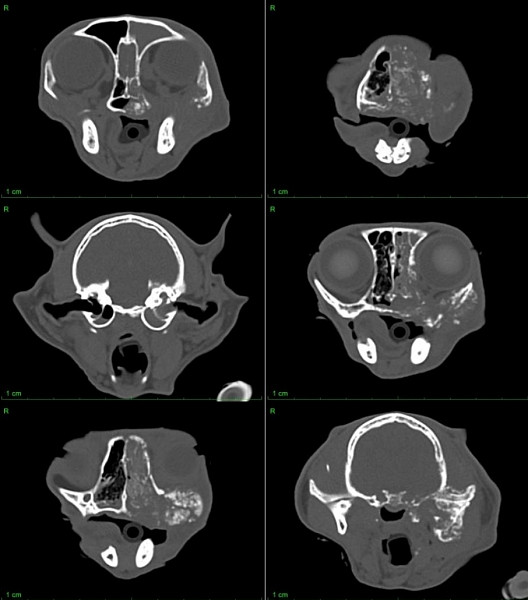

24 октября КТ.

Т.к интубация невозможна делать КТ было рискованно, однако выбора не было, КТ удалось сделать. Кости черепа целы.

(По результатам КТ выявлено объёмное новообразование челюсти, фронтит, этмоидит, балатерально средний отит. Присутствует птиализм, синдром хорнера левосторонний, истечение гнойно катарального типа из левой ноздри. Региоральные лимфоузлы пальпально спокойны. Pr исследование грудной клетки - признаки неопластического процесса не визуализированы.)

Но самое главное, что сейчас сделали ренген и уже начался активный лизис костей черепа, чего не было во время КТ.